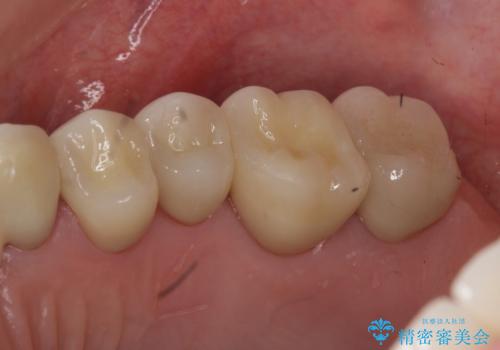

奥歯の被せ物のやり直し 精密根管治療

- 左上の一番奥の歯の根の治療を行いつつ、手前の歯の被せ物のやり直しも一緒に行いました。

手前の被せ物は、メタルボンドクラウンだったため、歯ぐきとの境目が黒くなっていたためやり直しを行いました。

オールジルコニアクラウンに変え、審美的な被せ物になりました。